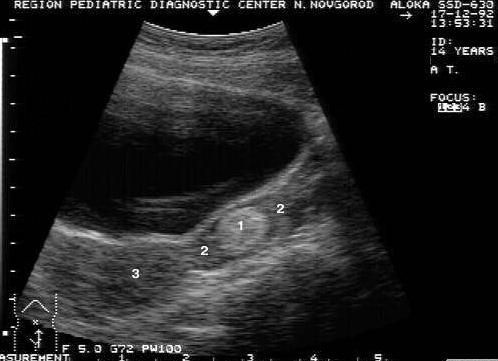

Часто в гинекологической практике встречаются кисты. В большинстве случаев они являются функциональными. Лютеиновая киста обычно имеет округлую форму и толстую стенку, интенсивный кровоток по периферии яичника. Ее размеры колеблются от 3 до 7 см. При этом ее внутреннее наполнение может быть абсолютно анэхогенным или содержать гиперэхогенные включения (кровяные сгустки). Как правило, лютеиновая киста регрессирует самопроизвольно на протяжении нескольких менструальных циклов.

Зрелые тератомы чаще всего имеют размеры от 2 до 12 см. Они отличаются друг от друга по внутреннему содержимому. На экране монитора может отражаться всего один гиперэхогенный компонент, представляющий собой жир, или несколько кистозных и гиперэхогенных участков, а также плотная область, дающая акустическую тень. Мелкоштриховыми влючениями или тонкими и длинными структурами с повышенной плотностью чаще всего являются волосы, находящиеся внутри дермоида. Иногда за ними прослеживается «хвост кометы».

- Зрелые опухоли, образующиеся из гоноцитов, развивающиеся в органе женской репродуктивной системы. Размеры образования варьируются в пределах 2-12 см. Включения отличаются своим содержимым. На мониторе УЗИ виден 1 гиперэхогенный компонент, представляющий жир, и плотная часть, от которой исходит акустическая тень.

На мониторе аппарата ультразвуковой диагностики гиперэхогенные образования выглядят как светлые или практически белые пятна. Они могут иметь вид линейных, точечных или объемных включений. Светлые пятна свидетельствуют о появлении структур с высокой плотностью, через которые не проходят ультразвуковые волны.

Неоднородная структура с гиперэхогенными включениями характерна для дермоидной кисты. В ее полости визуализируются эхозоны, характерные для скопления жировой, костной ткани, волос.

Чаще всего повышенная эхо-плотность образования в яичнике говорит о наличии кисты, содержащей элементы костей, волос, жира. Такая киста называется дермоидной и требует специального лечения.

Дермоидную кисту называют еще тератомой яичника. Она представляет собой специальную капсулу, которая содержит в себе всевозможные ткани, порою даже целую копну волос или кость. Откуда они появляются? Дело в том, что в ткани яичников каждой женщины имеются эмбриональные зачатки, и именно из них растет по неизвестным еще науке причинам дермоидная киста. Как правило, увеличивается это гиперэхогенное образование в яичнике медленно, женщина даже не ощущает никакого дискомфорта. Форму она имеет круглую или овально-вытянутую, а в диаметре колебаться от 5 до 15 см.